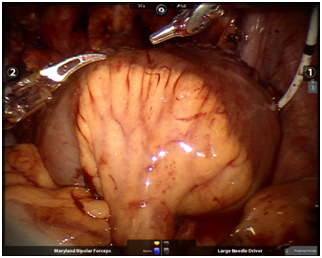

Benim robotik divertikülektomi operasyonu uyguladığım hasta 14 yaşında bir çocuk olgu idi. Sık idrara çıkma şikayeti bulunan hastada işeme sonrası artık idrar hacmi 300 ml gibi oldukça yüksekti. Sistografide mesane adeta iki ayrı bölüm şeklinde gözlenmekteydi. Hastaya yaptığım robotik eksizyon sonrası (resim 6) hastanın şikayetleri ve artık idrar miktarı toparladı.

Resim 6: Ameliyat esnasında çıkarttığım divertikül ve divertikülün ağzı görülmekte